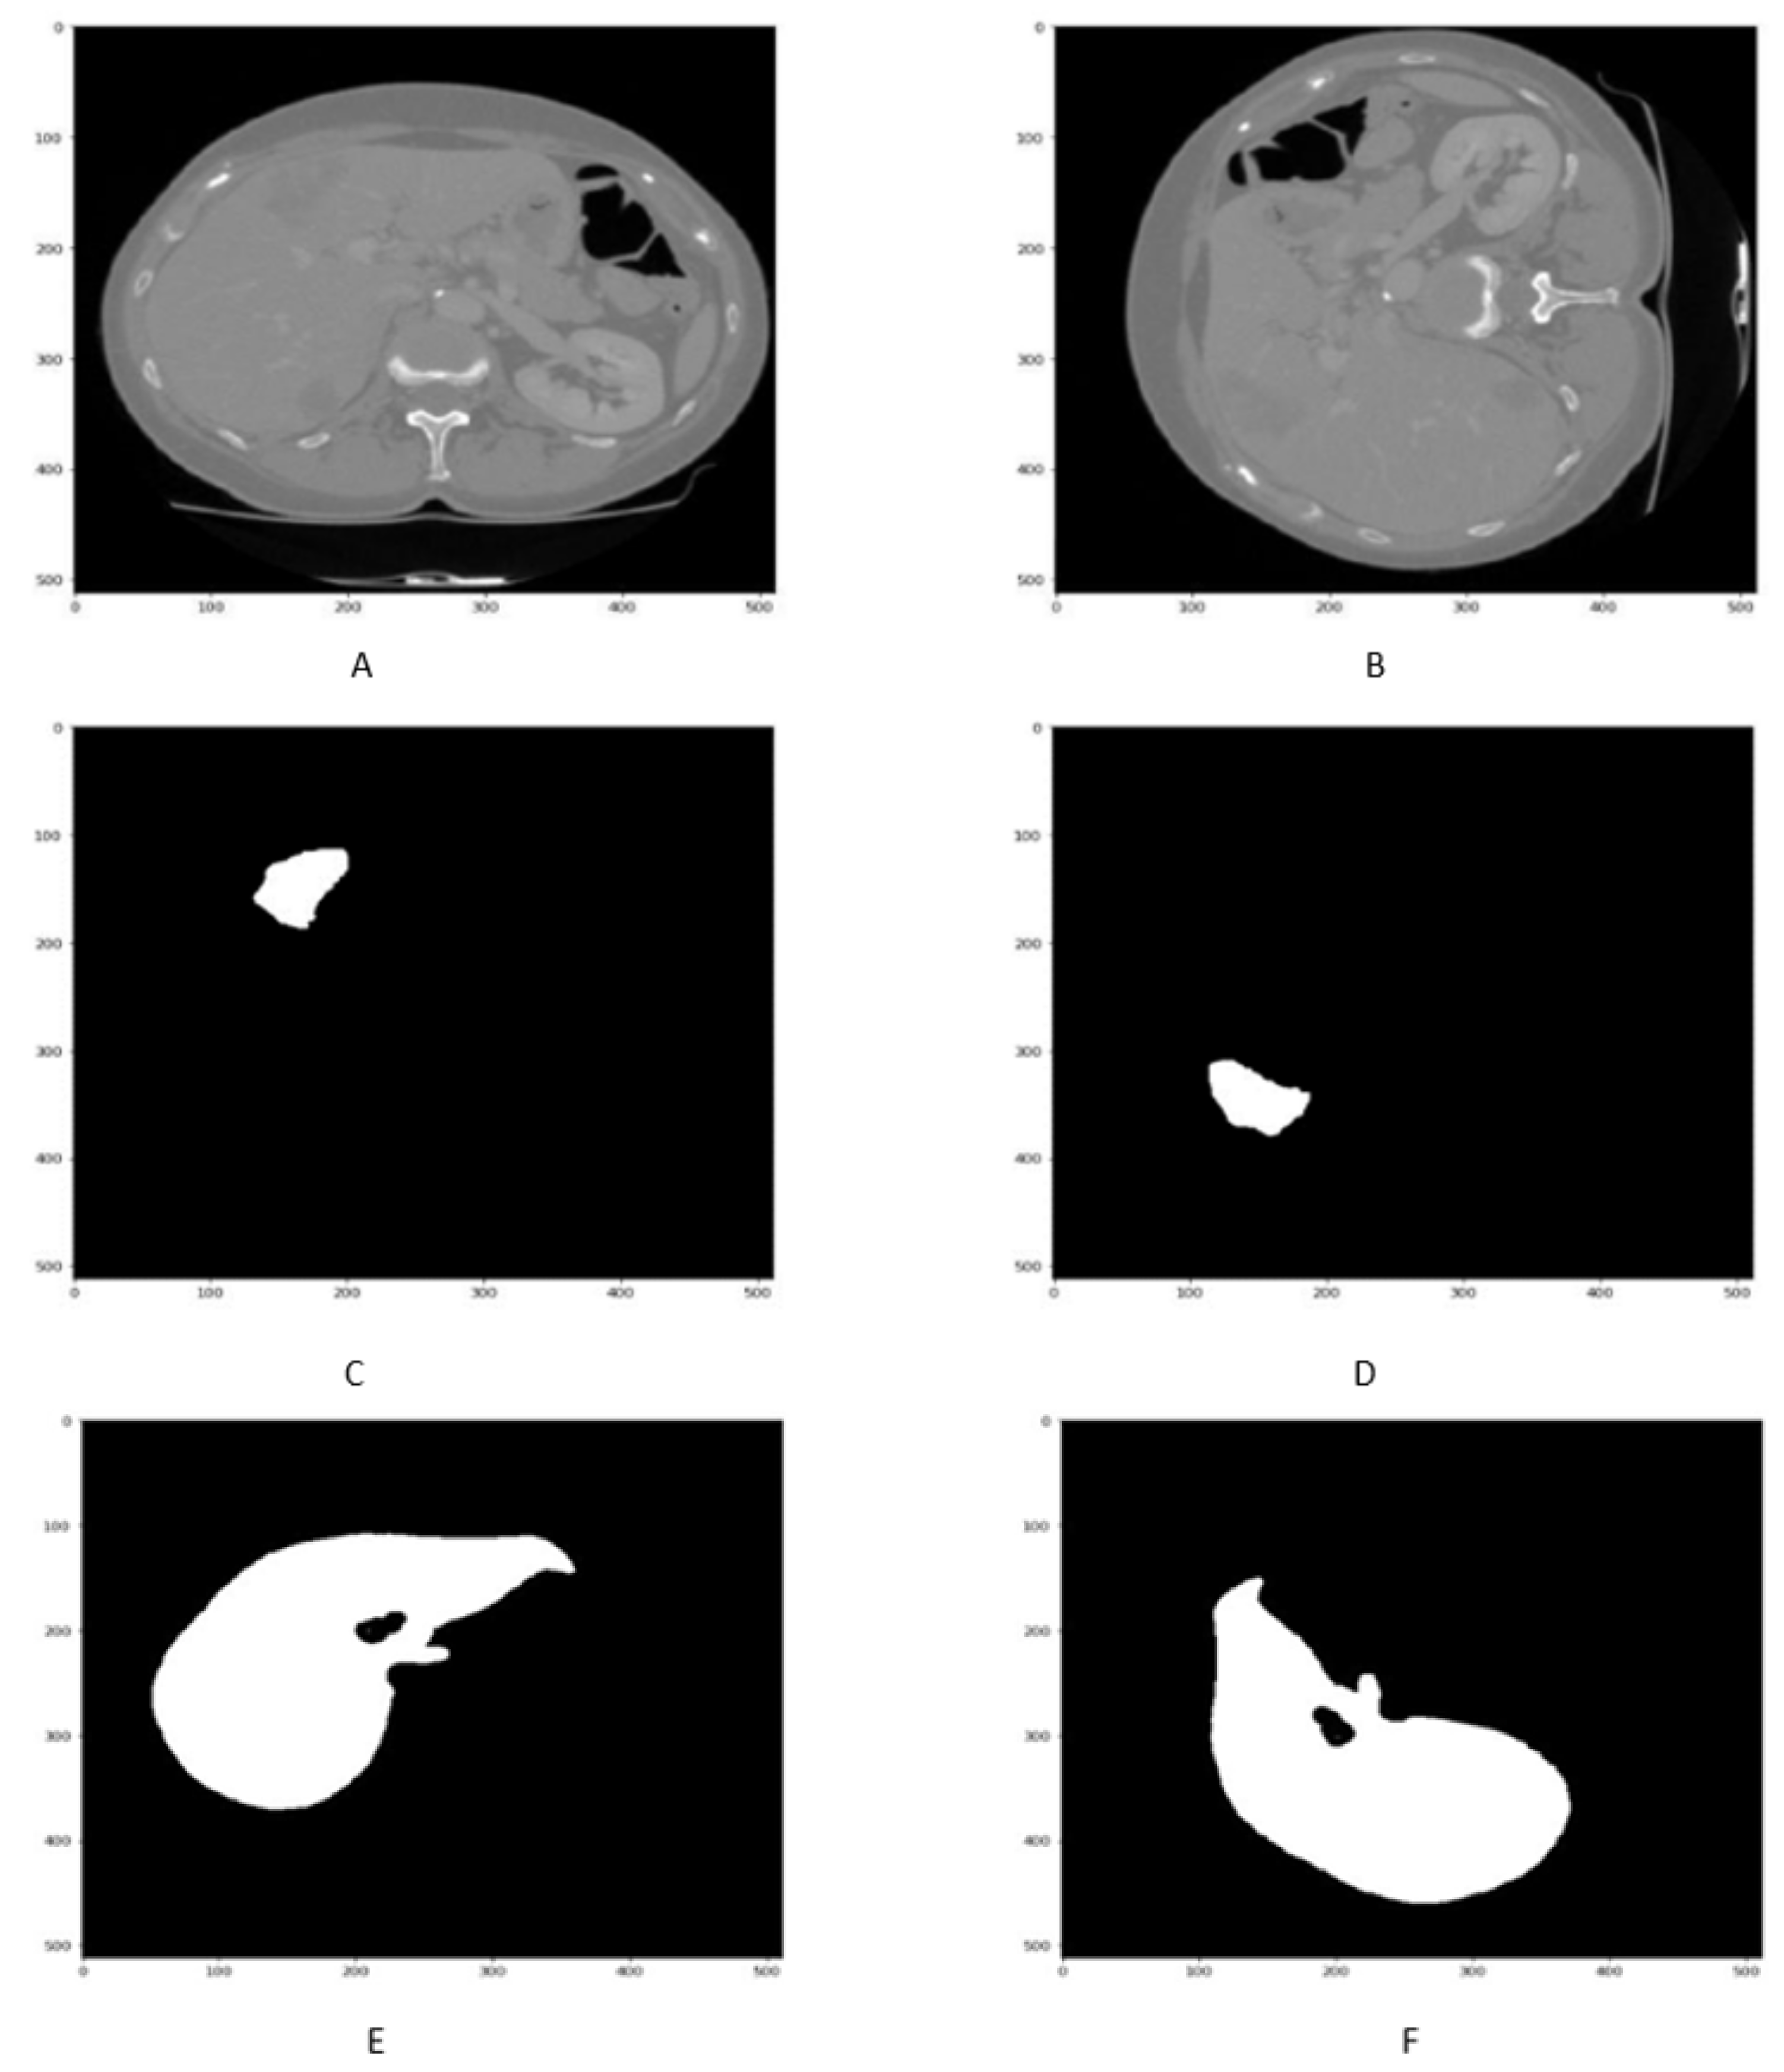

The rotation method of data augmentation involves rotating the image to a certain degree that can be considered a new image.Here, a 90 rotation of liver images along with its masks are performed as shown in Figure 5A–F.

Figure 5.

Figure shows that the liver slice and its masks before 90 in (A,C,E) rotation, While liver scan and its masks mask in (B,D,F) after rotation.